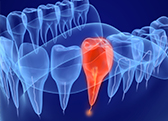

特にご自身の歯が長持ちするように虫歯や歯周病から予防することに力を入れております。